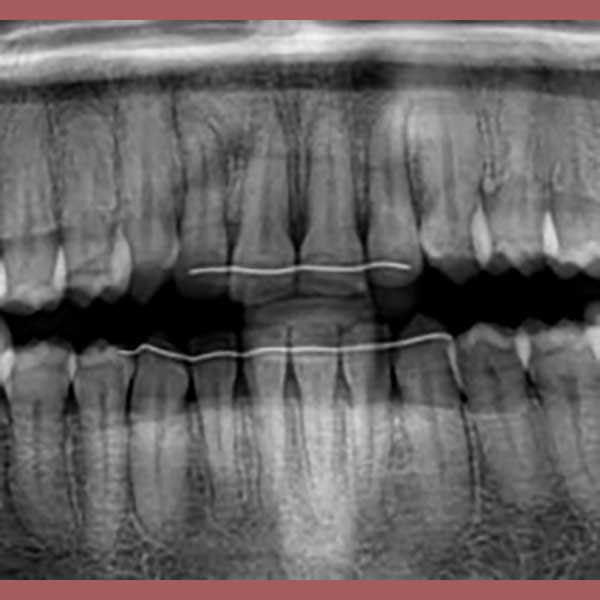

بعد الفحص وأخذ الصور الشعاعية، أوضح الدكتور خالد الكاتب أن الأنياب العلوية موجودة ولكنها منطمرة بالكامل في عظم الفك، بالإضافة لوجود ضاحك سفلي منطمر أيضاً. وبسبب كبر سن المريضة، كان لا بد من خطة علاج متكاملة: